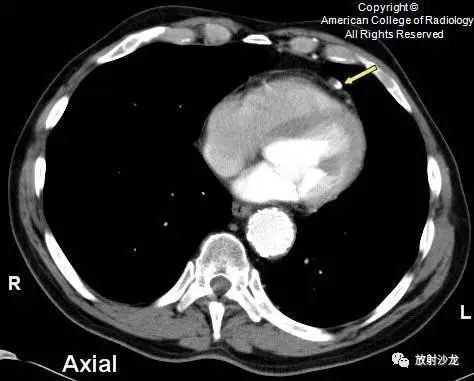

下图为患者六个月后的图像,显示病灶边缘部分出现钙化(箭头)。